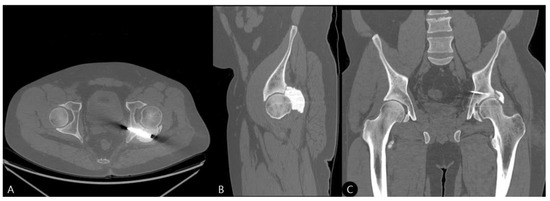

- 21 Months: AP pelvic radiographs showed excellent maintenance of joint space and a stable construct without loosening (Figure 9). The patient’s functional outcome was excellent, reporting no pain during daily activities, with only mild discomfort during deep squatting. The mHHS was 85/100.